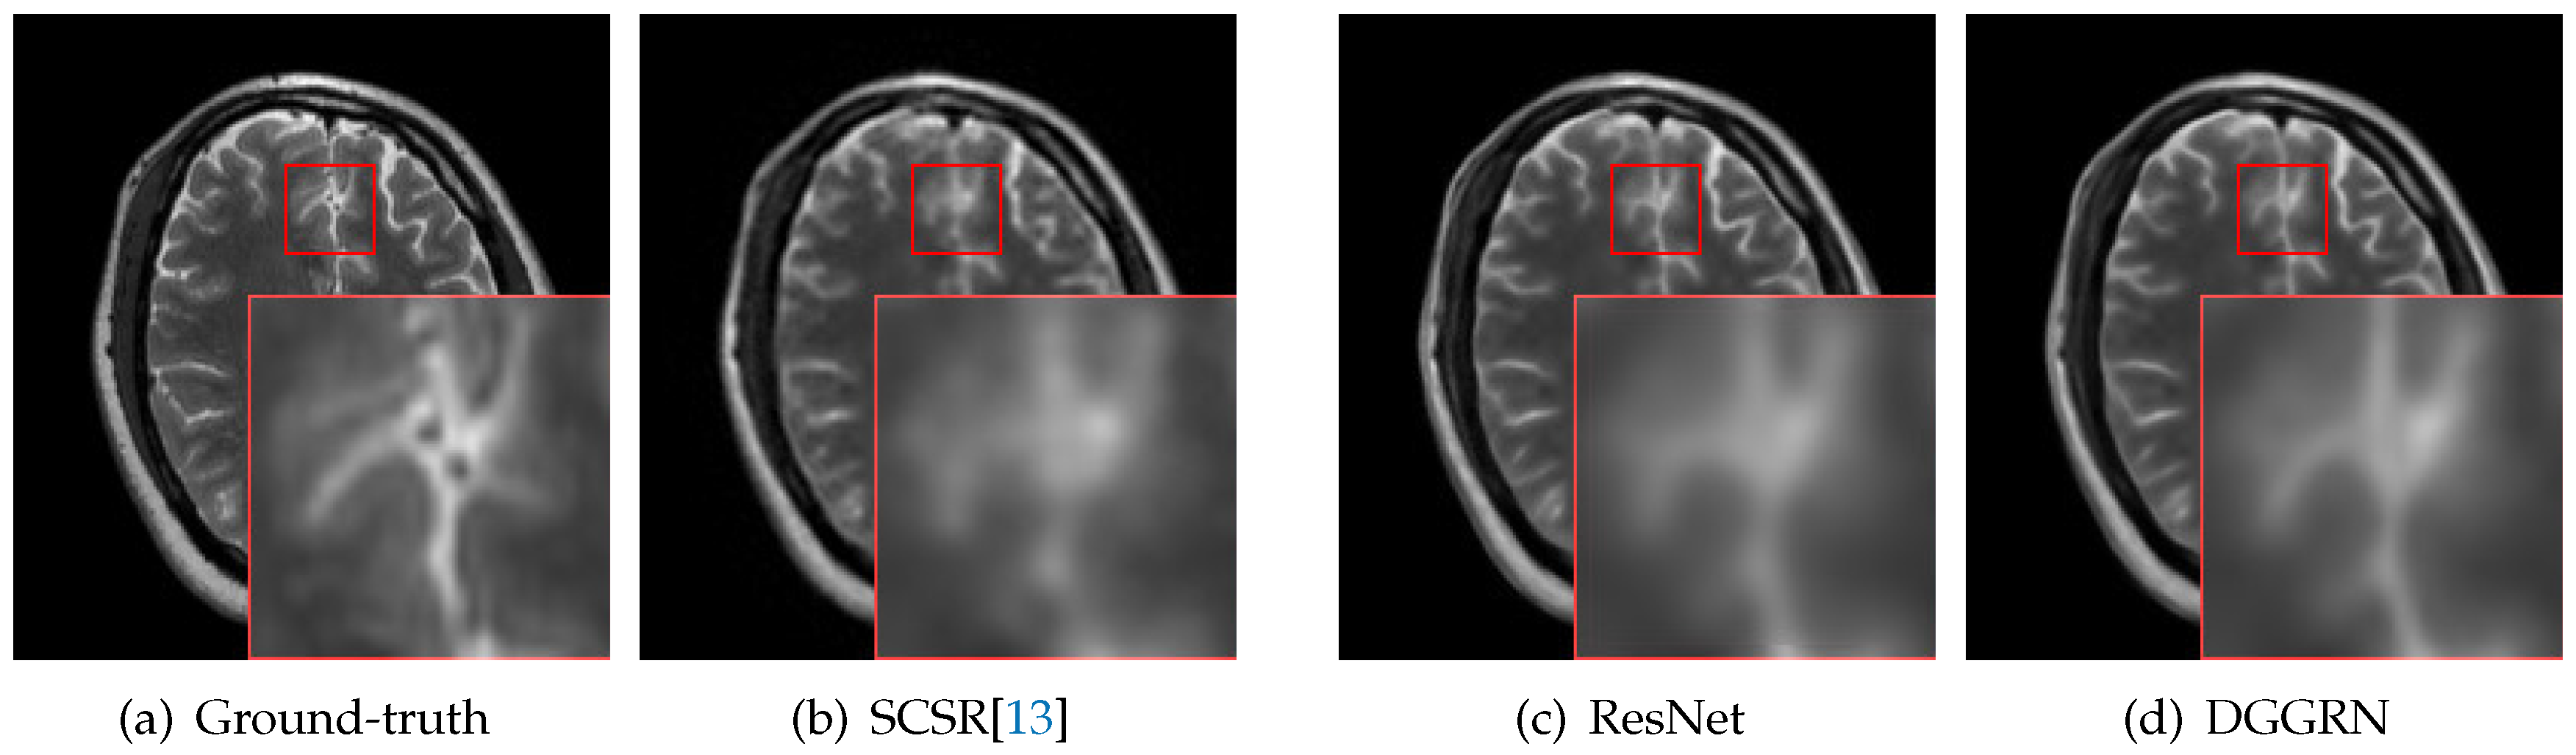

4.3. Comparison with State-of-the-Art Methods

5. Discussion